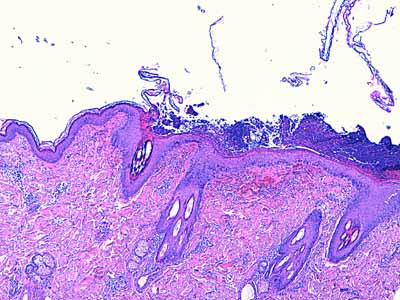

Photo 9 (Hémalun Eosine X 40) : Les pustules sous-cornées qui parsèment l’épiderme,

peuvent ponter l’abouchement de plusieurs follicules pileux voisins.

Légendes de la Photo 9 :

- Double flèche noire : épiderme

- Double flèche pointillée noire : derme

- Pointes de flèche turquoise : délimitation de la pustule intra-épidermique sous-cornée qui ponte l’abouchement de trois unités folliculo-sébacées

- Pointes de flèche jaune : toit rompu de la pustule (fines lamelles de kératine orthokératosique)

- Cercles marrons : glandes sébacées

- Étoiles rouges pleines : vaisseaux sanguins

- Étoiles rouges vides : follicules pileux

- Étoiles turquoises : glandes sudorales apocrines épitrichiales

- Flèche orange : infiltrat dermique de topographie péri-vasculaire